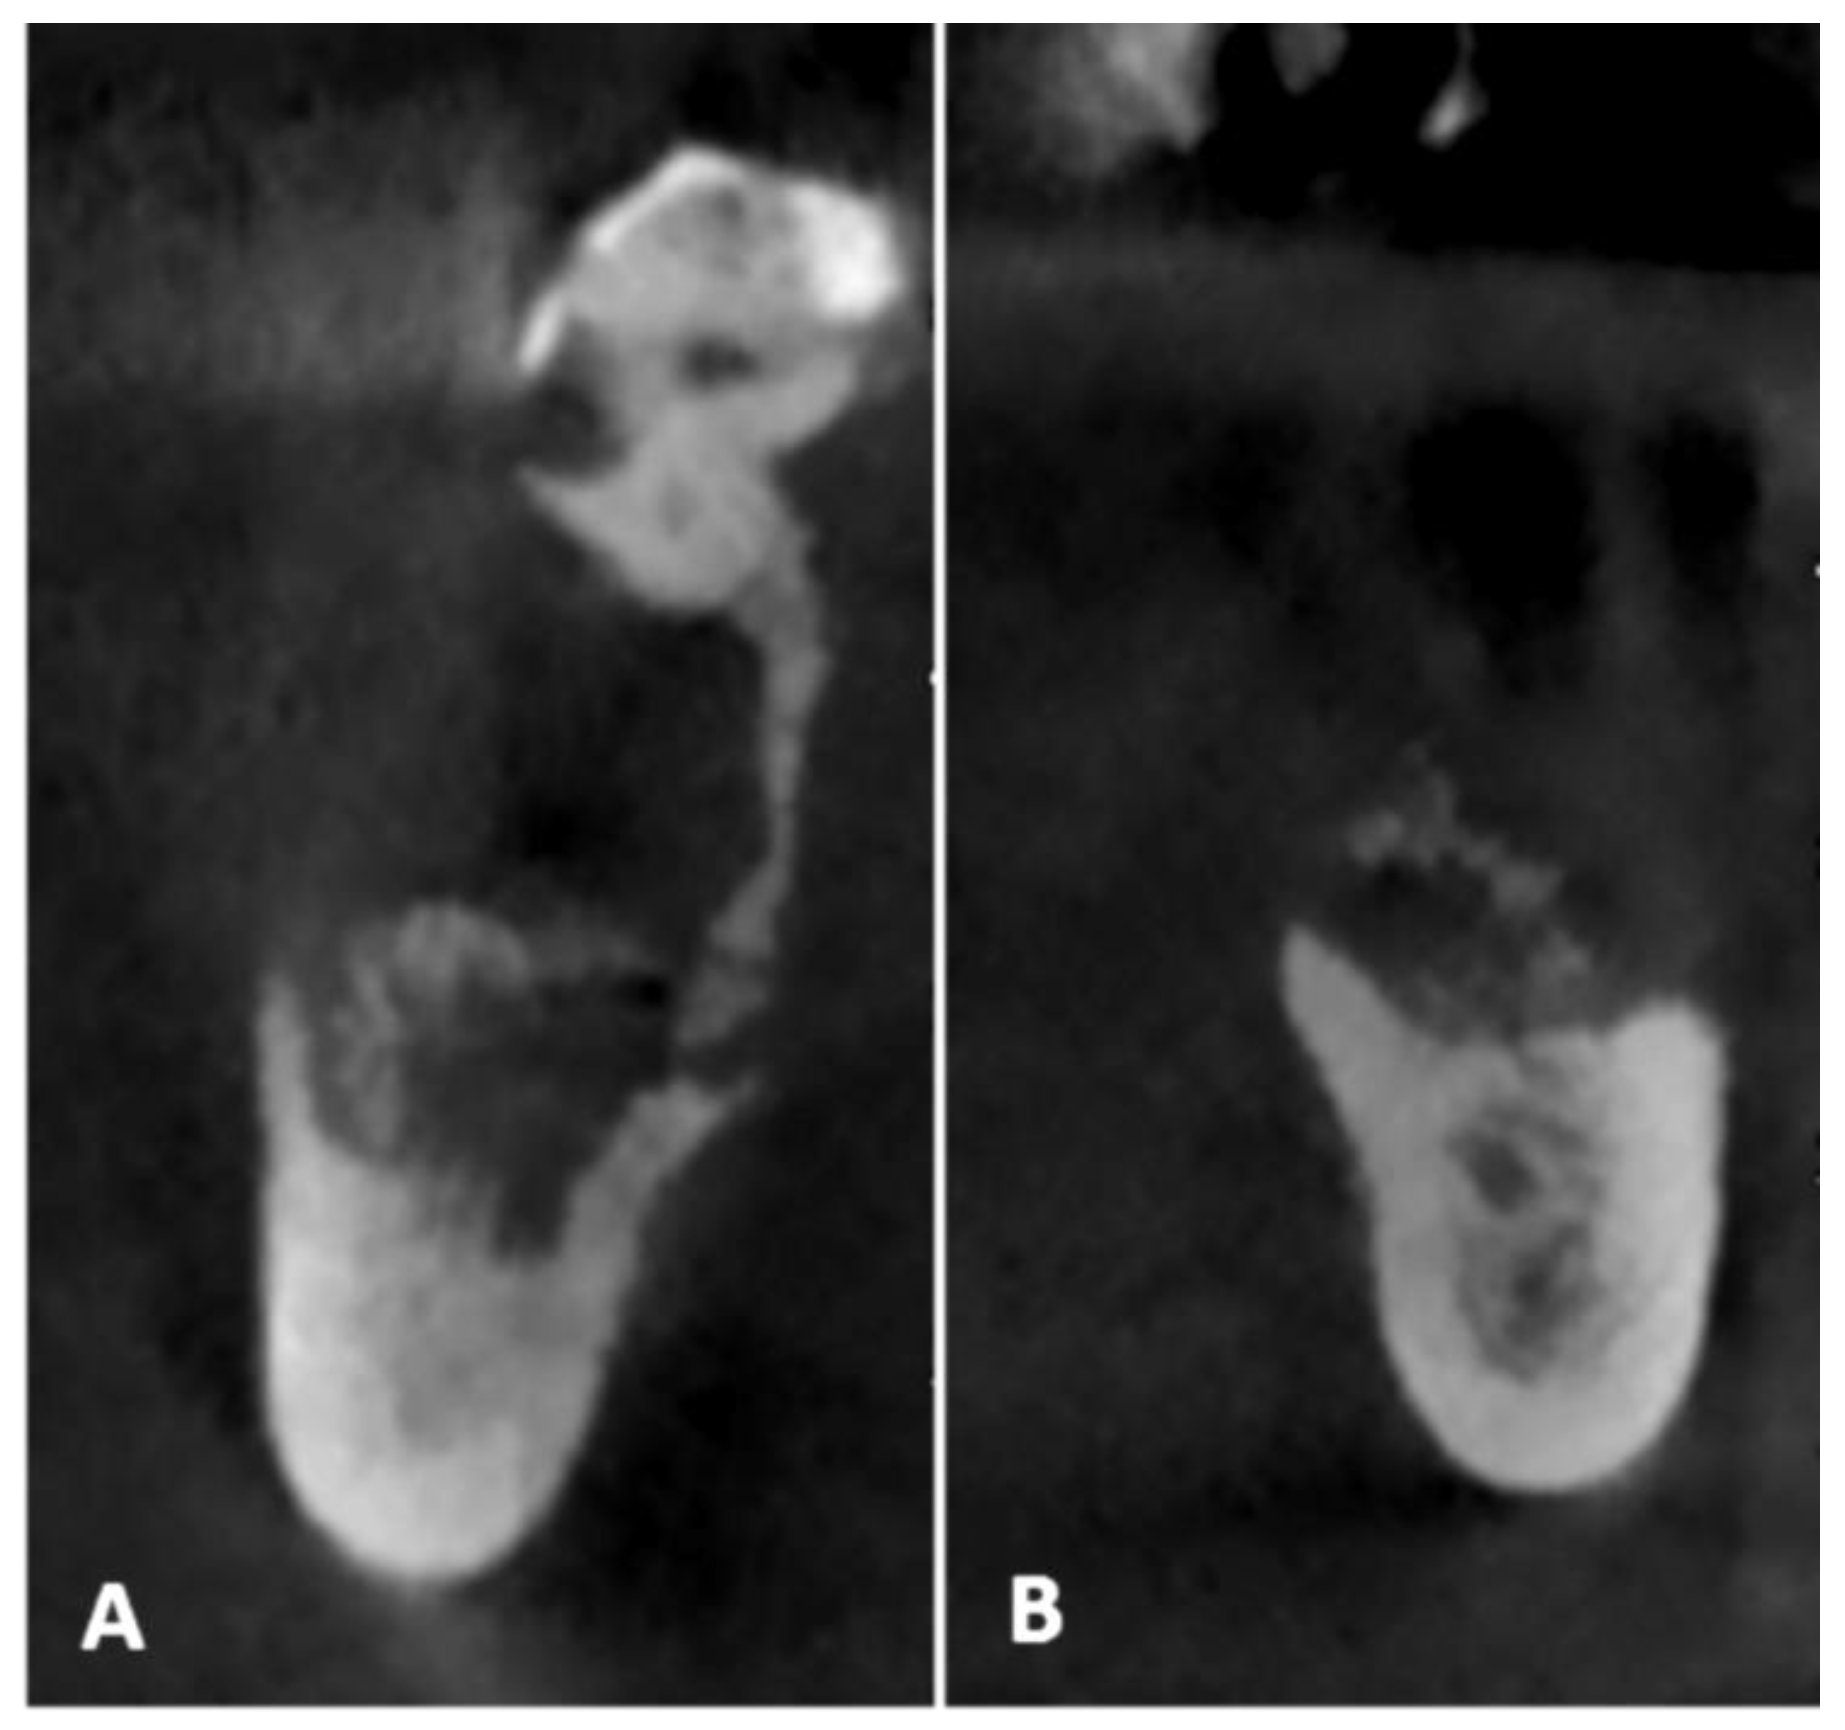

2.1. Case Presentation

- Pre-operative evaluation. The patient undergoes a cone-beam CT exam with a reference plate containing the fiducial markers, fixed on his inferior teeth. The Digital Imaging and Communications in Medicine (DICOM) were imported into the navigation software.

- Surgery timing. The surgeon can follow in real time the ultrasonic tip position onto the system screen displaying the CBCT images and safely identify and remove the necrotic bone surrounding the inferior alveolar nerve on the right side.